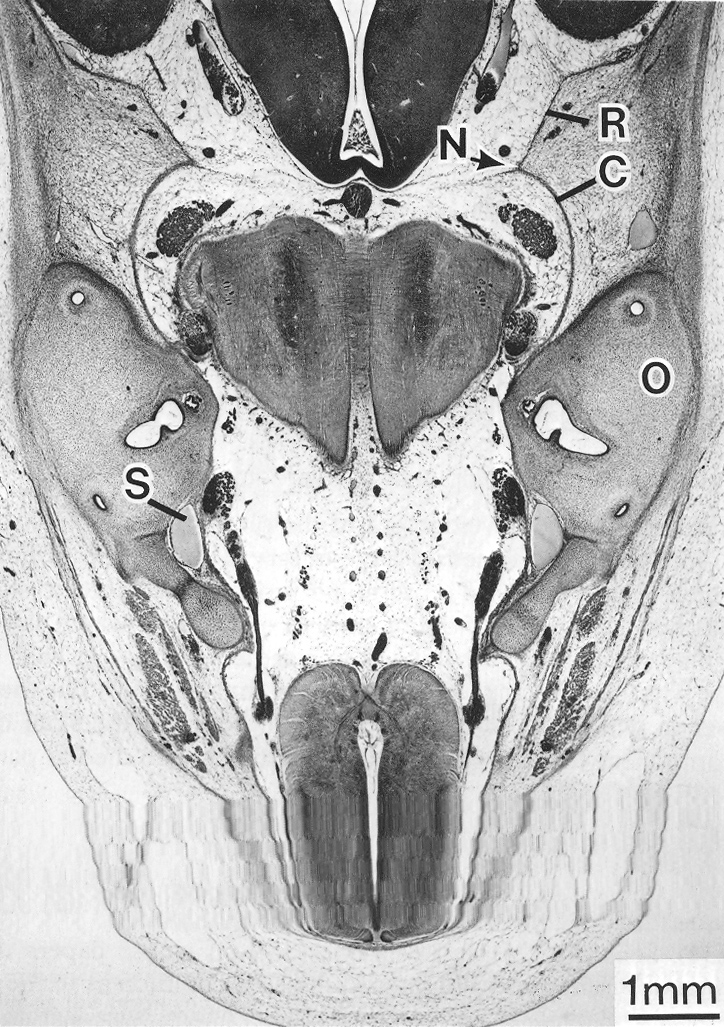

Dural limiting layer, pachymeninx, and skeleton at stage 23.

Keywords: dural limiting layer, pachymeninx, skeleton

Source: The Virtual Human Embryo.